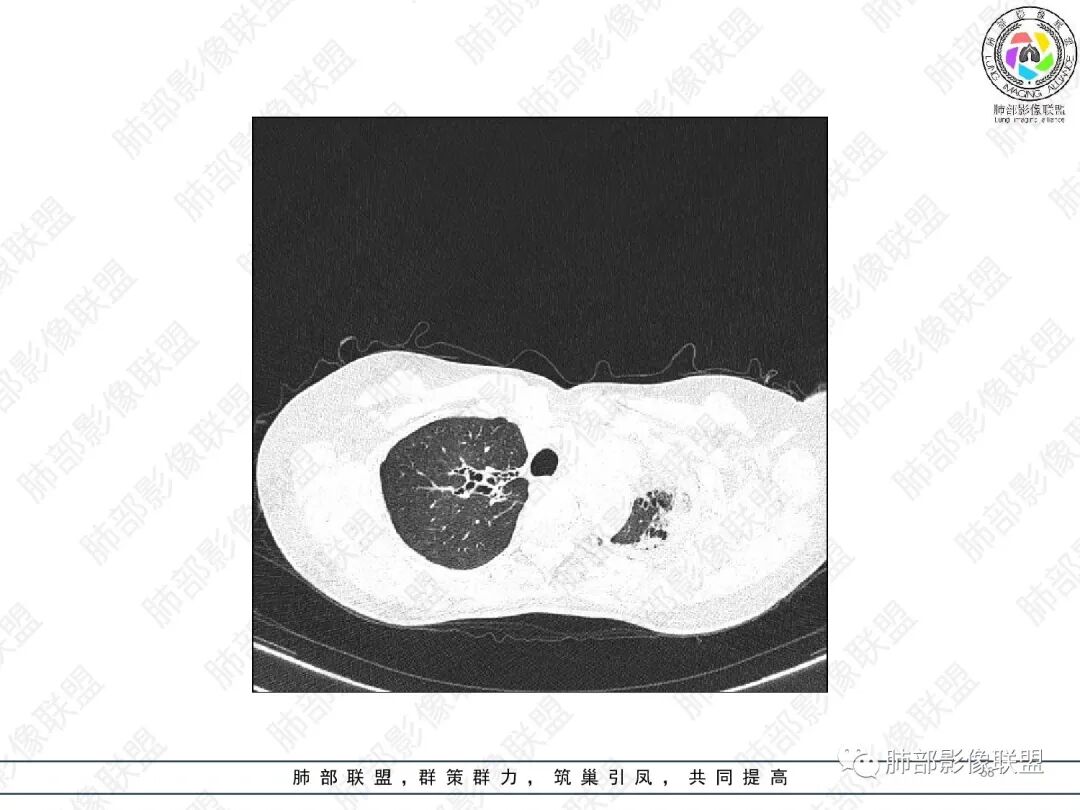

2.胸部CT:右肺上叶及中叶不规则块状影,沿支气管走行方向指套样影,支气阻塞湖嵌塞,腔内可见高密度影。灶周可见磨玻璃,外围见结节影及树芽征。左肺体积缩小,见不规则条索影、胸膜增厚,纵隔牵拉左移。

3.综合分析:结合患者病史及胸部CT主要鉴别ABPA(右肺上叶不规则块影,指套样顺延支气管方向,抗结核治疗1年,肺部病灶仍明显)及继发性肺结核TB(右肺上叶不规则肿块,其可见高密影,边缘模糊,周围卫星灶、树芽征,沿支气管爬行)。

胸部影像学的特异性改变:随着胸部高分辨率CT(HRCT)的普及,ABPA常见肺部影像表现包括黏液嵌塞、支气管扩张、小叶中心性结节、树芽征和马赛克征等。根据是否有中心性支气管扩张,ABPA可分为变态反应性支气管肺曲霉病-血清IgE增高型(ABPA-S)和变态反应性支气管肺曲霉病-中心性支气管扩张型(ABPA-CB)。气道黏液嵌塞在ABPA很常见,胸部HRCT上表现为指套征或牙膏征。气道黏液栓通常为低密度影,但20%也可为高密度黏液影(high-attenuation mucus,HAM),定义为气道内黏液栓密度高于脊柱旁肌肉的 HRCT值,这也成为ABPA特征性的影像表现之一,外周细支气管黏液阻塞可见“树芽征”。中央性支气管扩张曾一直是ABPA诊断标准之一,但其用于诊断ABPA的敏感度仅为37%。此外,33%~43%的中央性支气管扩张也可延伸至外周,26%~39%的ABPA只有周围性支气管扩张。因此,目前认为中央性支气管扩张应视为ABPA的并发症,而非其诊断标准。